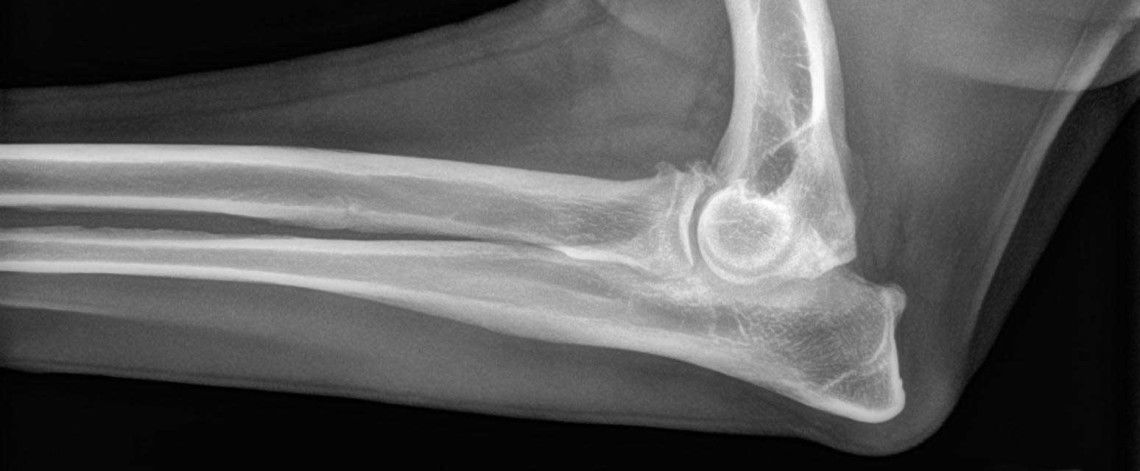

Forelimb

Conditions affecting the forelimb, including the shoulder, elbow, and wrist joints.